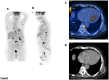

The International Myeloma Working Group (IMWG)recommends FDG PET/CT (Fluoro-Deoxy-glucose Positron Emission Tomography/Computed Tomography) as the gold standard imaging modality for initial evaluation and response to therapy assessment in multiple myeloma. In fact, FDG PET/CT, provides multiple useful indexes to risk-stratify patients and has significant prognostic value. However, multiple myeloma remains a complex disease to interpret on imaging. The Italian myeloma criteria for PET use (IMPeTUs) were proposed to standardize FDG PET/CT reading in multiple myeloma. In this communication an overview on IMPeTUs is provided as well as some examples of application.